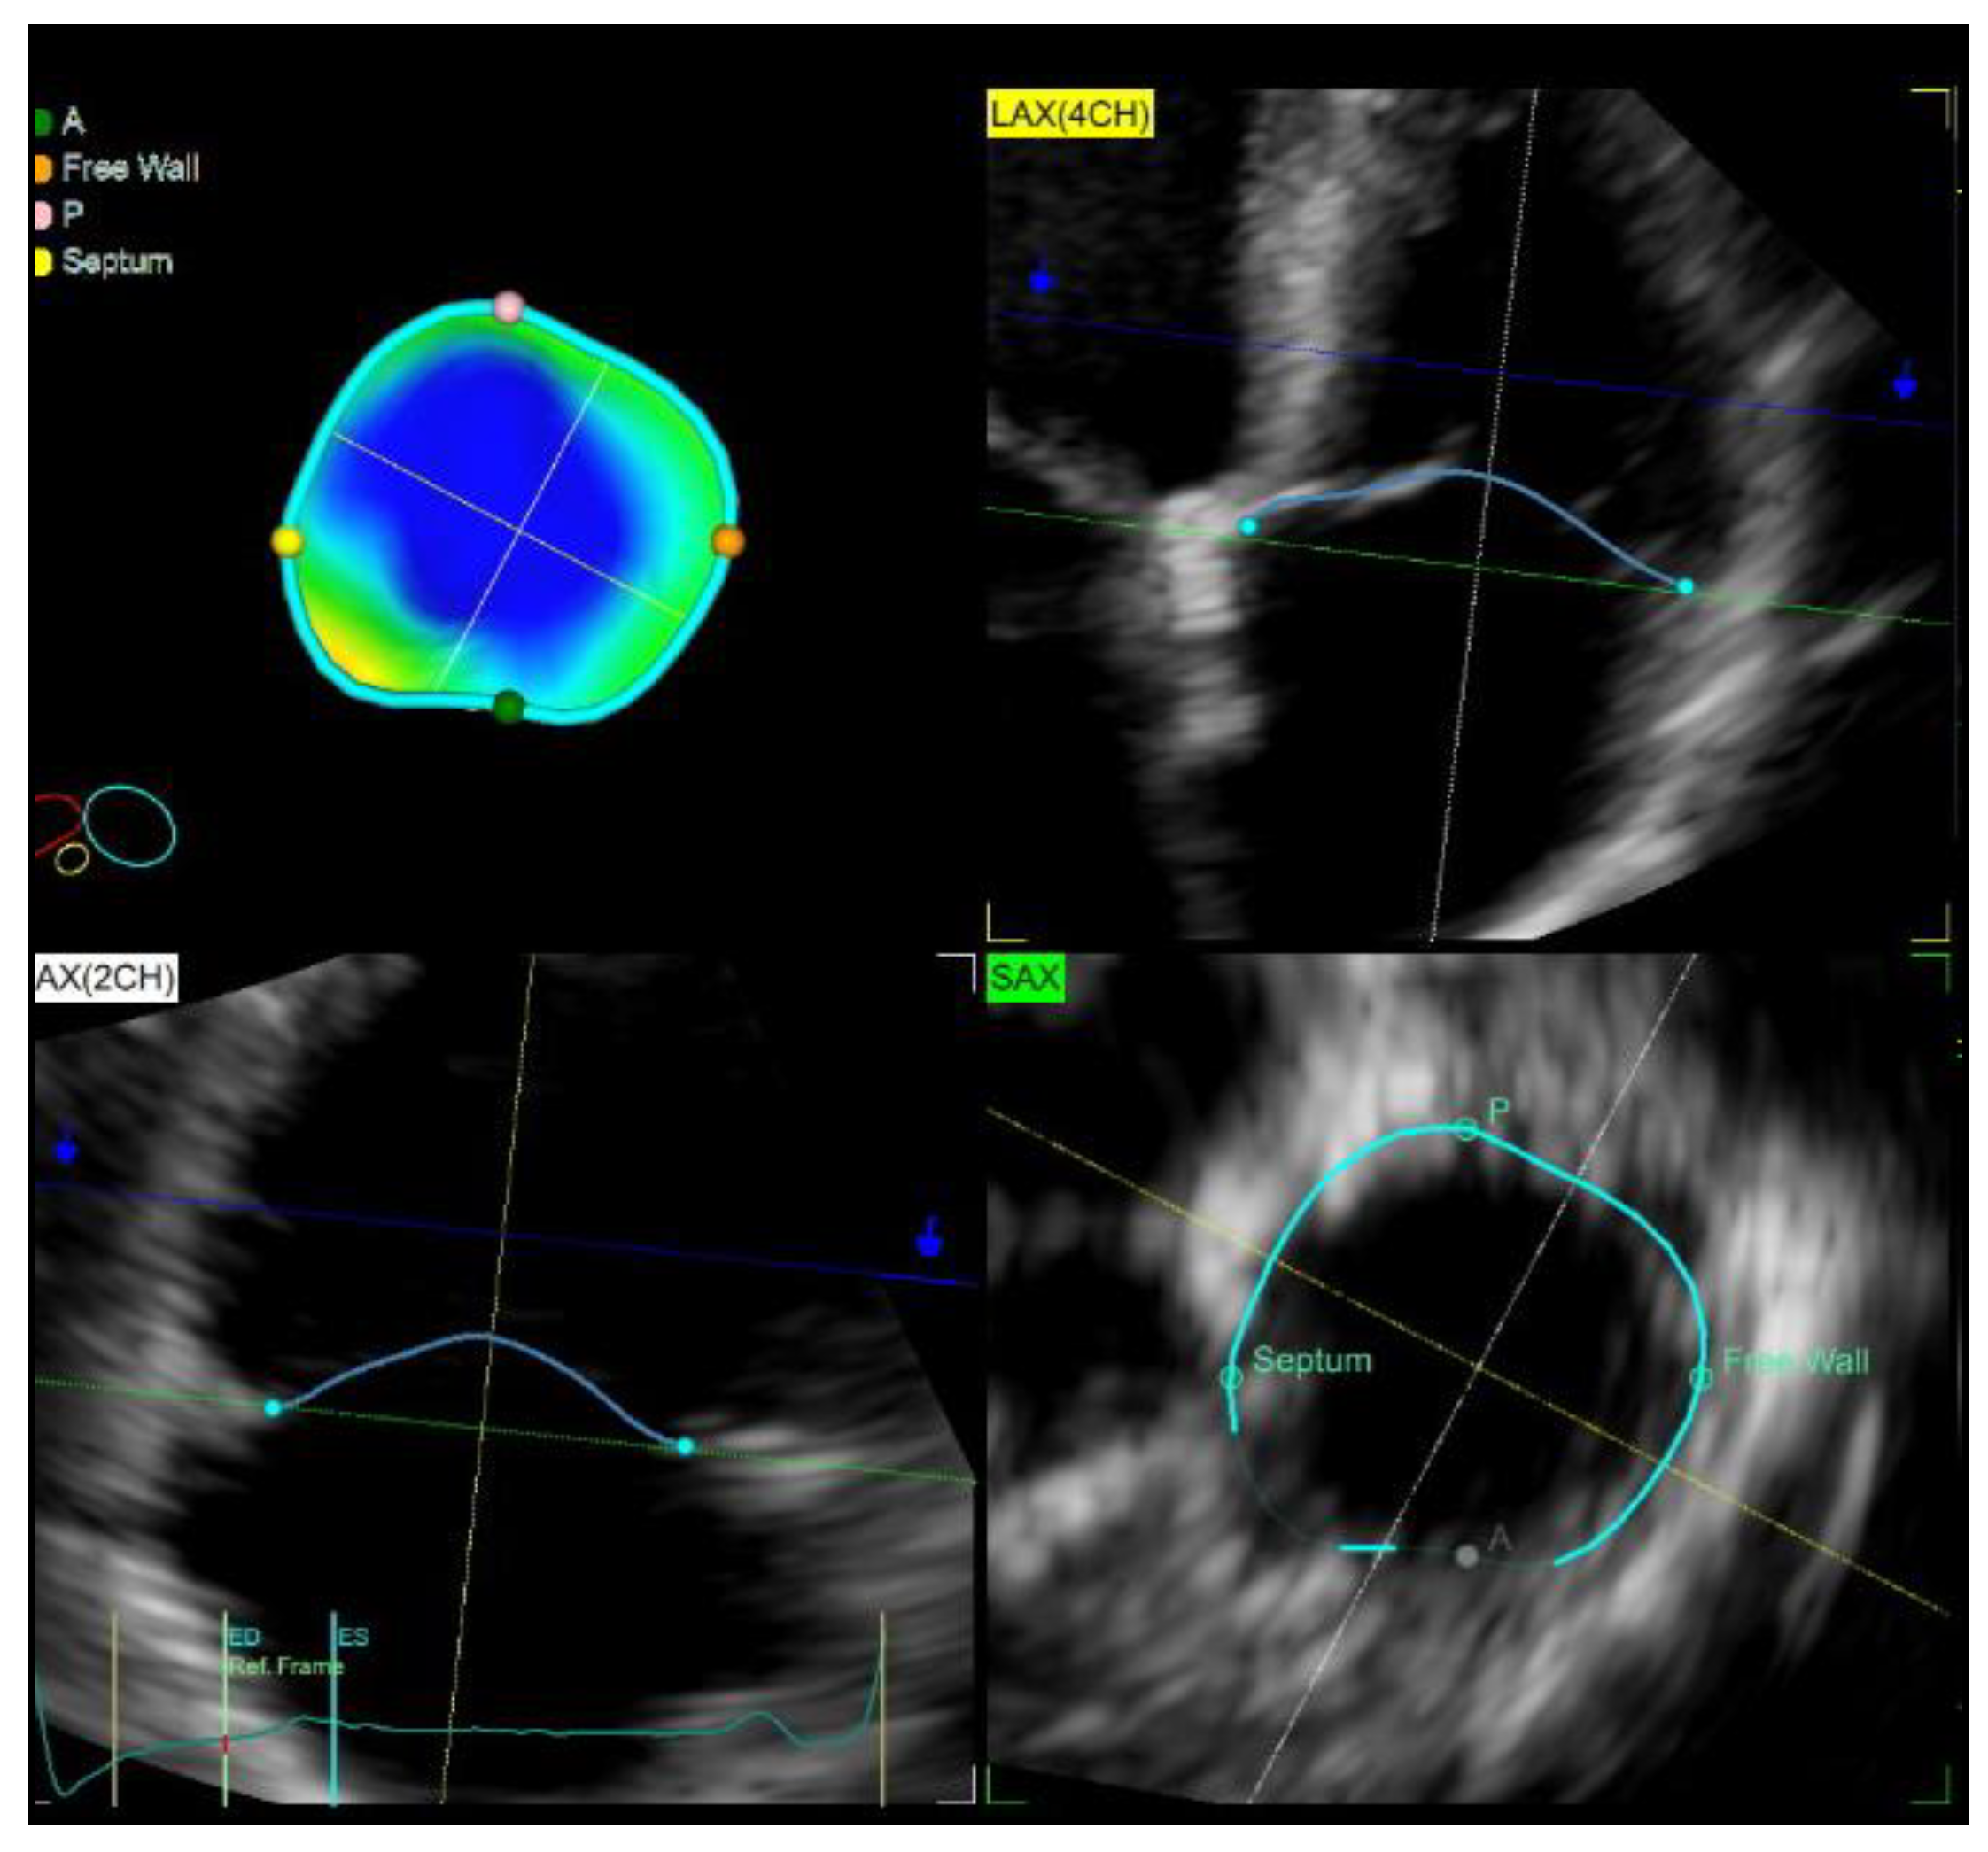

| TV parameters | ||||||

| TA area, cm2 | 14.3 (4.4) | 13.2 (3.4) | 8.1 (0.93) | 0.649 | <0.001 | <0.001 |

| TA area index (cm2/m2) | 7.13 (2.25) | 6.88 (2.17) | 4.45 (0.97) | 0.713 | <0.001 | <0.001 |

| TA perimeter, mm | 130 (23) | 133 (17) | 102 (7.5) | 0.979 | <0.001 | <0.001 |

| Minor Axis Diastolic TA Diameter, mm | 39 (8) | 36 (6) | 27 (3.5) | 0.222 | <0.001 | <0.001 |

| TV Leaflet Coaptation point Height, mm | 9 (5.5) | 13 (3) | 6.5 (2) | <0.001 | 0.012 | <0.001 |

| TV Leaflet Tenting Volume, mL | 3.9 (2) | 5 (2.9) | 1.55 (0.25) | 0.025 | <0.001 | <0.001 |

| TV Sphericity Index, % | 83.67 (11.33) | 80 (14.04) | 73.61 (12.4) | 0.04 | 0.002 | 0.13 |